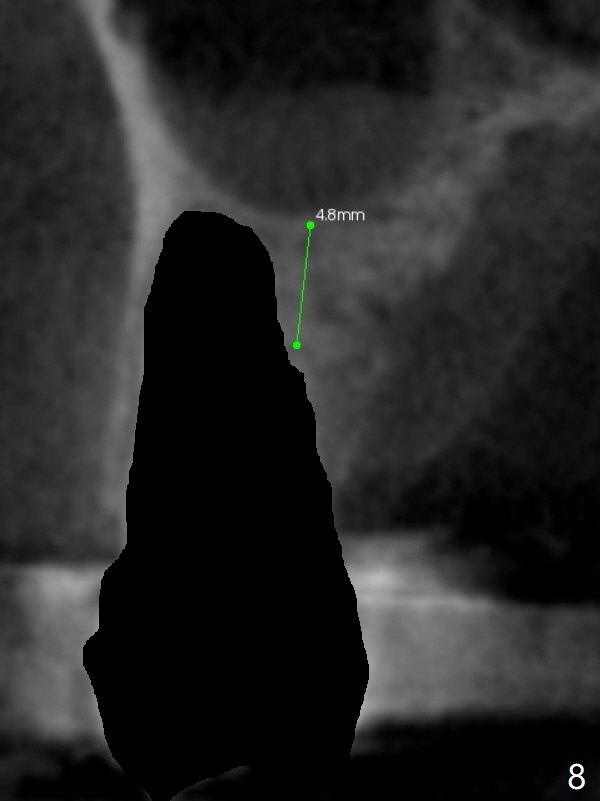

After extraction of the tooth #4, osteotomy is initiated in the middle of the palatal slope (Fig.6), followed immediately by change in trajectory (Fig.7). The depth of the osteotomy is ~ 5 mm (Fig.8), followed by 2.8 mm round bur from Sinus Lift Master Kit. Press the burs palatally. Following Vanilla Graft (red circles), place a 3.5 or 4.0x17 mm dummy and final implants (Fig.3,9,10).